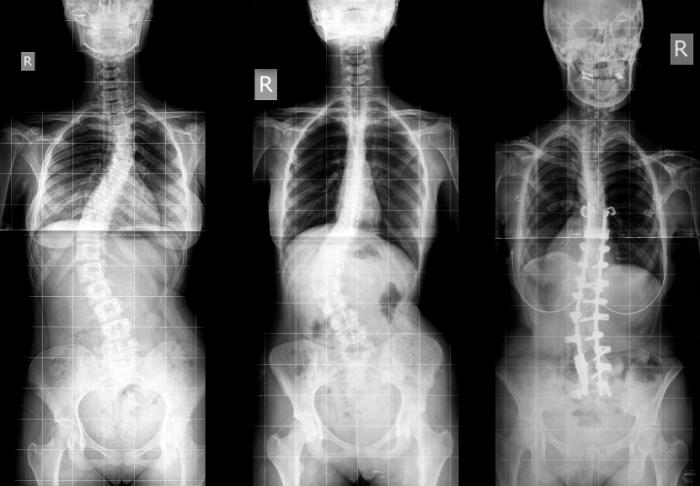

Scoliosis

A person who has scoliosis will have a C- or S-shaped curve in their spine. It can appear at any age, but it is generally present from the age of 10 to 12 years, or during the teens, but even infants can sometimes have symptoms. The reasons for the change in shape are not known, but some cases are linked to muscular dystrophy, spina bifida, cerebral palsy, or a birth defect. A structural curve is permanent and maybe because of another condition. A nonstructural curve is temporary and it is very likely to disappear with time. Children who have mild scoliosis are monitored very closely, generally with X-rays, to see if the curve is getting worse or not. In many cases, no treatment is required. Some children will be required to wear a brace to stop the curve from further worsening.

In as many as 80% of cases, doctors don’t find the particular reason for a curved spine. Scoliosis without a known source is known as “idiopathic.” Some kinds of scoliosis do have clear sources. Doctors generally divide those curves into two kinds - structural and nonstructural. In nonstructural scoliosis, the spine works normally, but looks curved; there are a number of reasons, for this occurs such muscle spasms, inflammations like appendicitis, and as one leg’s being longer than the other. When these causes are treated, this type of scoliosis generally goes away. In structural scoliosis, the curve of the spine is rigid and hence can’t be reversed.

• Pre-operative imaging and Diagnostics: Full-Spine X-rays, MRI or CT Scans, and pulmonary function tests.

• X-Rays